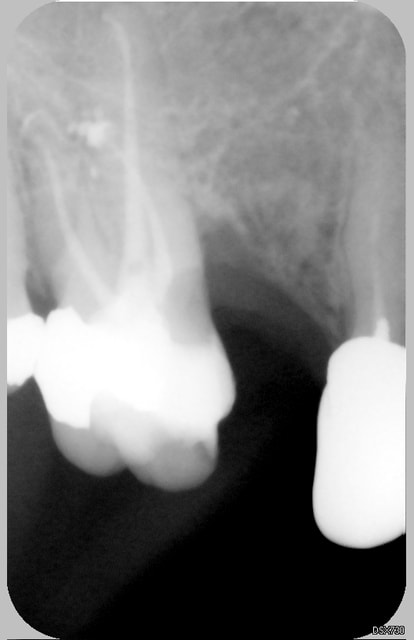

cf une radio par exemple 10-2006 parmi tant d'autre. Dent traitée pour une pulpite en 2005 sans cause flagrante. Radio prise pour faire une reconstitution prothétique. Lyse radiculaire M sous-gingivale. Palpation à la sonde : paroi dure et lisse

tout à fait ok avec ton observation et pour revenir au cas de la 37 je pense qu"elle est condamnée et que la lesion mesiale n'est pas de la carie mais "resorbtive" origine des cellules grignoteuses??desmodonte?pulpe?

j'ai essayé de traiter une dent qui ressemblait à celle ci et malgré la reprise du trt racine l'inlay core et la cr la resorbtion à continuée et tt a foiré

voir ds rubrique endo à propos des anesthesies intraligtaires et autres/ces images de resorbtions bizarres ne sont elles pas les cicatrices de nos anesthesies intraligt ou intraseptales?

vernal

13/06/2007 à 14h40

Dans le cas de la 16 donnée en exemple, mon collègue ne fait aucune intraligamentaire uniquement des paraapicales sur les sup